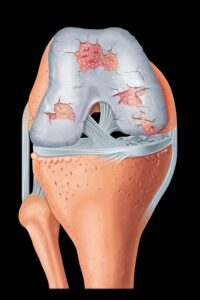

Im allgemeinen Sprachgebrauch auch „Wohlstandskrankheit” oder „Zipperlein” genannt, in der medizinischen Literatur „Arthritis urica” oder „Hyperurikämie”. Es handelt sich um eine Stoffwechselkrankheit, die durch erhöhte Konzentrationen von Harnsäure bedingt ist, einem natürlichen Abbauprodukt des Eiweißstoffwechsels der Körperzellen(sogenannte „Purine”). Der Harnsäurespiegel im Blut kann erhöht sein wegen vermehrter Zufuhr (zum Beispiel purinreiche Nahrung, Alkohol), vermehrter Bildung im Körper (z.B. angeborene Enzymdefekte) oder eine verminderte Ausscheidung über die Nieren (zum Beispiel Nierenkrankheiten, Medikamente). Meist kommen mehrere dieser Mechanismen zum Tragen, bevor eine Gicht entsteht. Durch Auskristallisierung der Harnsäure, vor allem in kühlen Körperregionen (Großzehengrundgelenk, Ohrknorpel), entstehen entzündliche Knoten („Tophus”). Bei fortbestehender, bzw. unbehandelter Harnsäureerhöhung kann die Gicht fast alle großen und kleinen Gelenke betreffen.  Das Geschlechtsverhältnis beträgt männlich : weiblich 8 : 1. Durch die Ablagerung von Harnsäurekristallen im Nierengewebe kann auch zu einer zusätzlichen Schädigung der Nieren kommen.

Das Geschlechtsverhältnis beträgt männlich : weiblich 8 : 1. Durch die Ablagerung von Harnsäurekristallen im Nierengewebe kann auch zu einer zusätzlichen Schädigung der Nieren kommen.

Symptome: Typischerweise kommt es zu einem akut, über Nacht auftretenden Gichtanfall der Großzehe („Podagra”), der zu einer schmerzhaften entzündlichen Schwellung des Großzehen- grundgelenkes führt, einschließlich einer ausgeprägten Schmerzempfindlichkeit der Haut.

Therapie: Die Behandlung des akuten Gichtanfalls besteht in Ruhigstellung, Kühlung und Gabe von Medikamenten (Etoricoxib). Der Prophylaxe des Gichtanfalls dienen diätetische Maßnahmen (Vermeiden von Hülsenfrüchten und Fleisch, insbesondere Innereien) und die Reduktion des Alkoholkonsums, vor allem Bier! Wird die Gicht durch diese Maßnahmen nicht gebessert, ist eine dauernde Gabe von Medikamenten notwendig, welche die Bildung der Harnsäure im Körper vermindern (Allopurinol).

Prognose: Der Verlauf der Erkrankung ist meist günstig, schwere Verlaufsformen sind selten. Die individuelle Beratung umfasst das Essverhalten und den Alkoholkonsum im Alltag. Begleitende Maßnahmen wie z. B. Gewichtsreduktion, regelmäßige sportliche Aktivität. Die Gicht bedarf der regelmäßigen ärztlichen Kontrolle (Blutabnahmen: Harnsäurespiegel) und einer intensiven, langandauernden Behandlung.